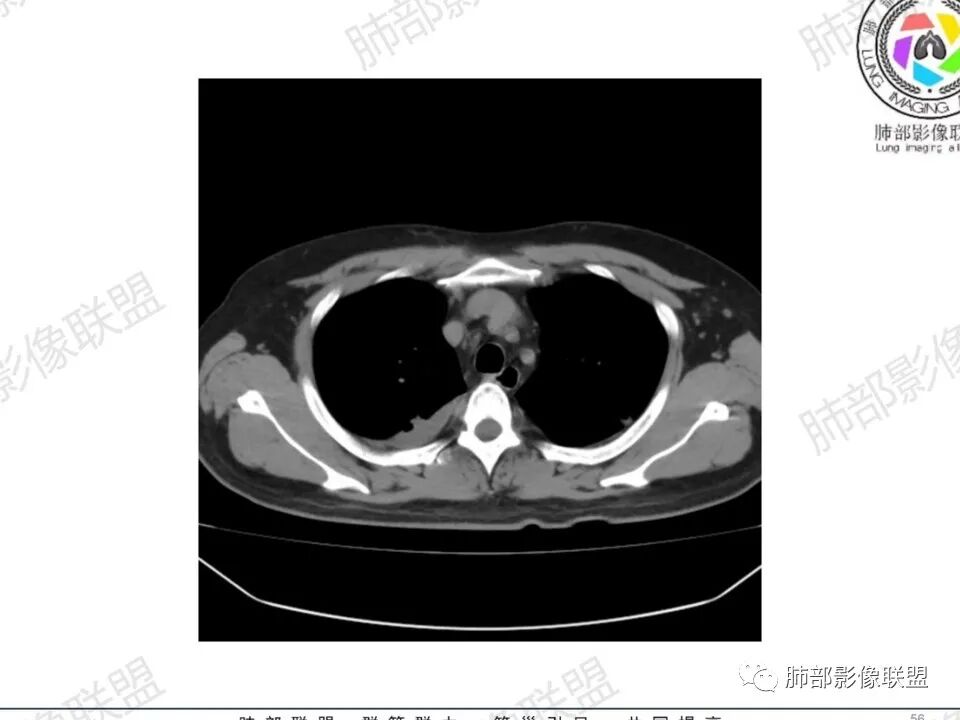

双肺多发结节,胸膜下为主,部分可见空洞。左肺上叶尖后段结节较大,分叶毛刺,周围可见长条索及小斑片影,内空洞比较光滑,内侧壁可见支气管通过。右肺下叶后基底段不张实变,后侧积液,右侧水平裂积液,右侧膈胸膜纵膈胸膜增厚积液,右侧侧胸膜肥厚,考虑1:一元金葡。2二元:金葡,左肺上叶结核。

中年男性,左手中指及胸壁疼痛伴发热来诊,影像见双肺多发结节,胸膜下分布为主,部分结节可见空洞,边缘模糊。左肺上叶尖后段结节较大。右肺下叶后基底段不张实变,右侧叶间裂及右侧胸腔积液,右侧侧胸膜肥厚。考虑金葡菌感染,血播SPE。